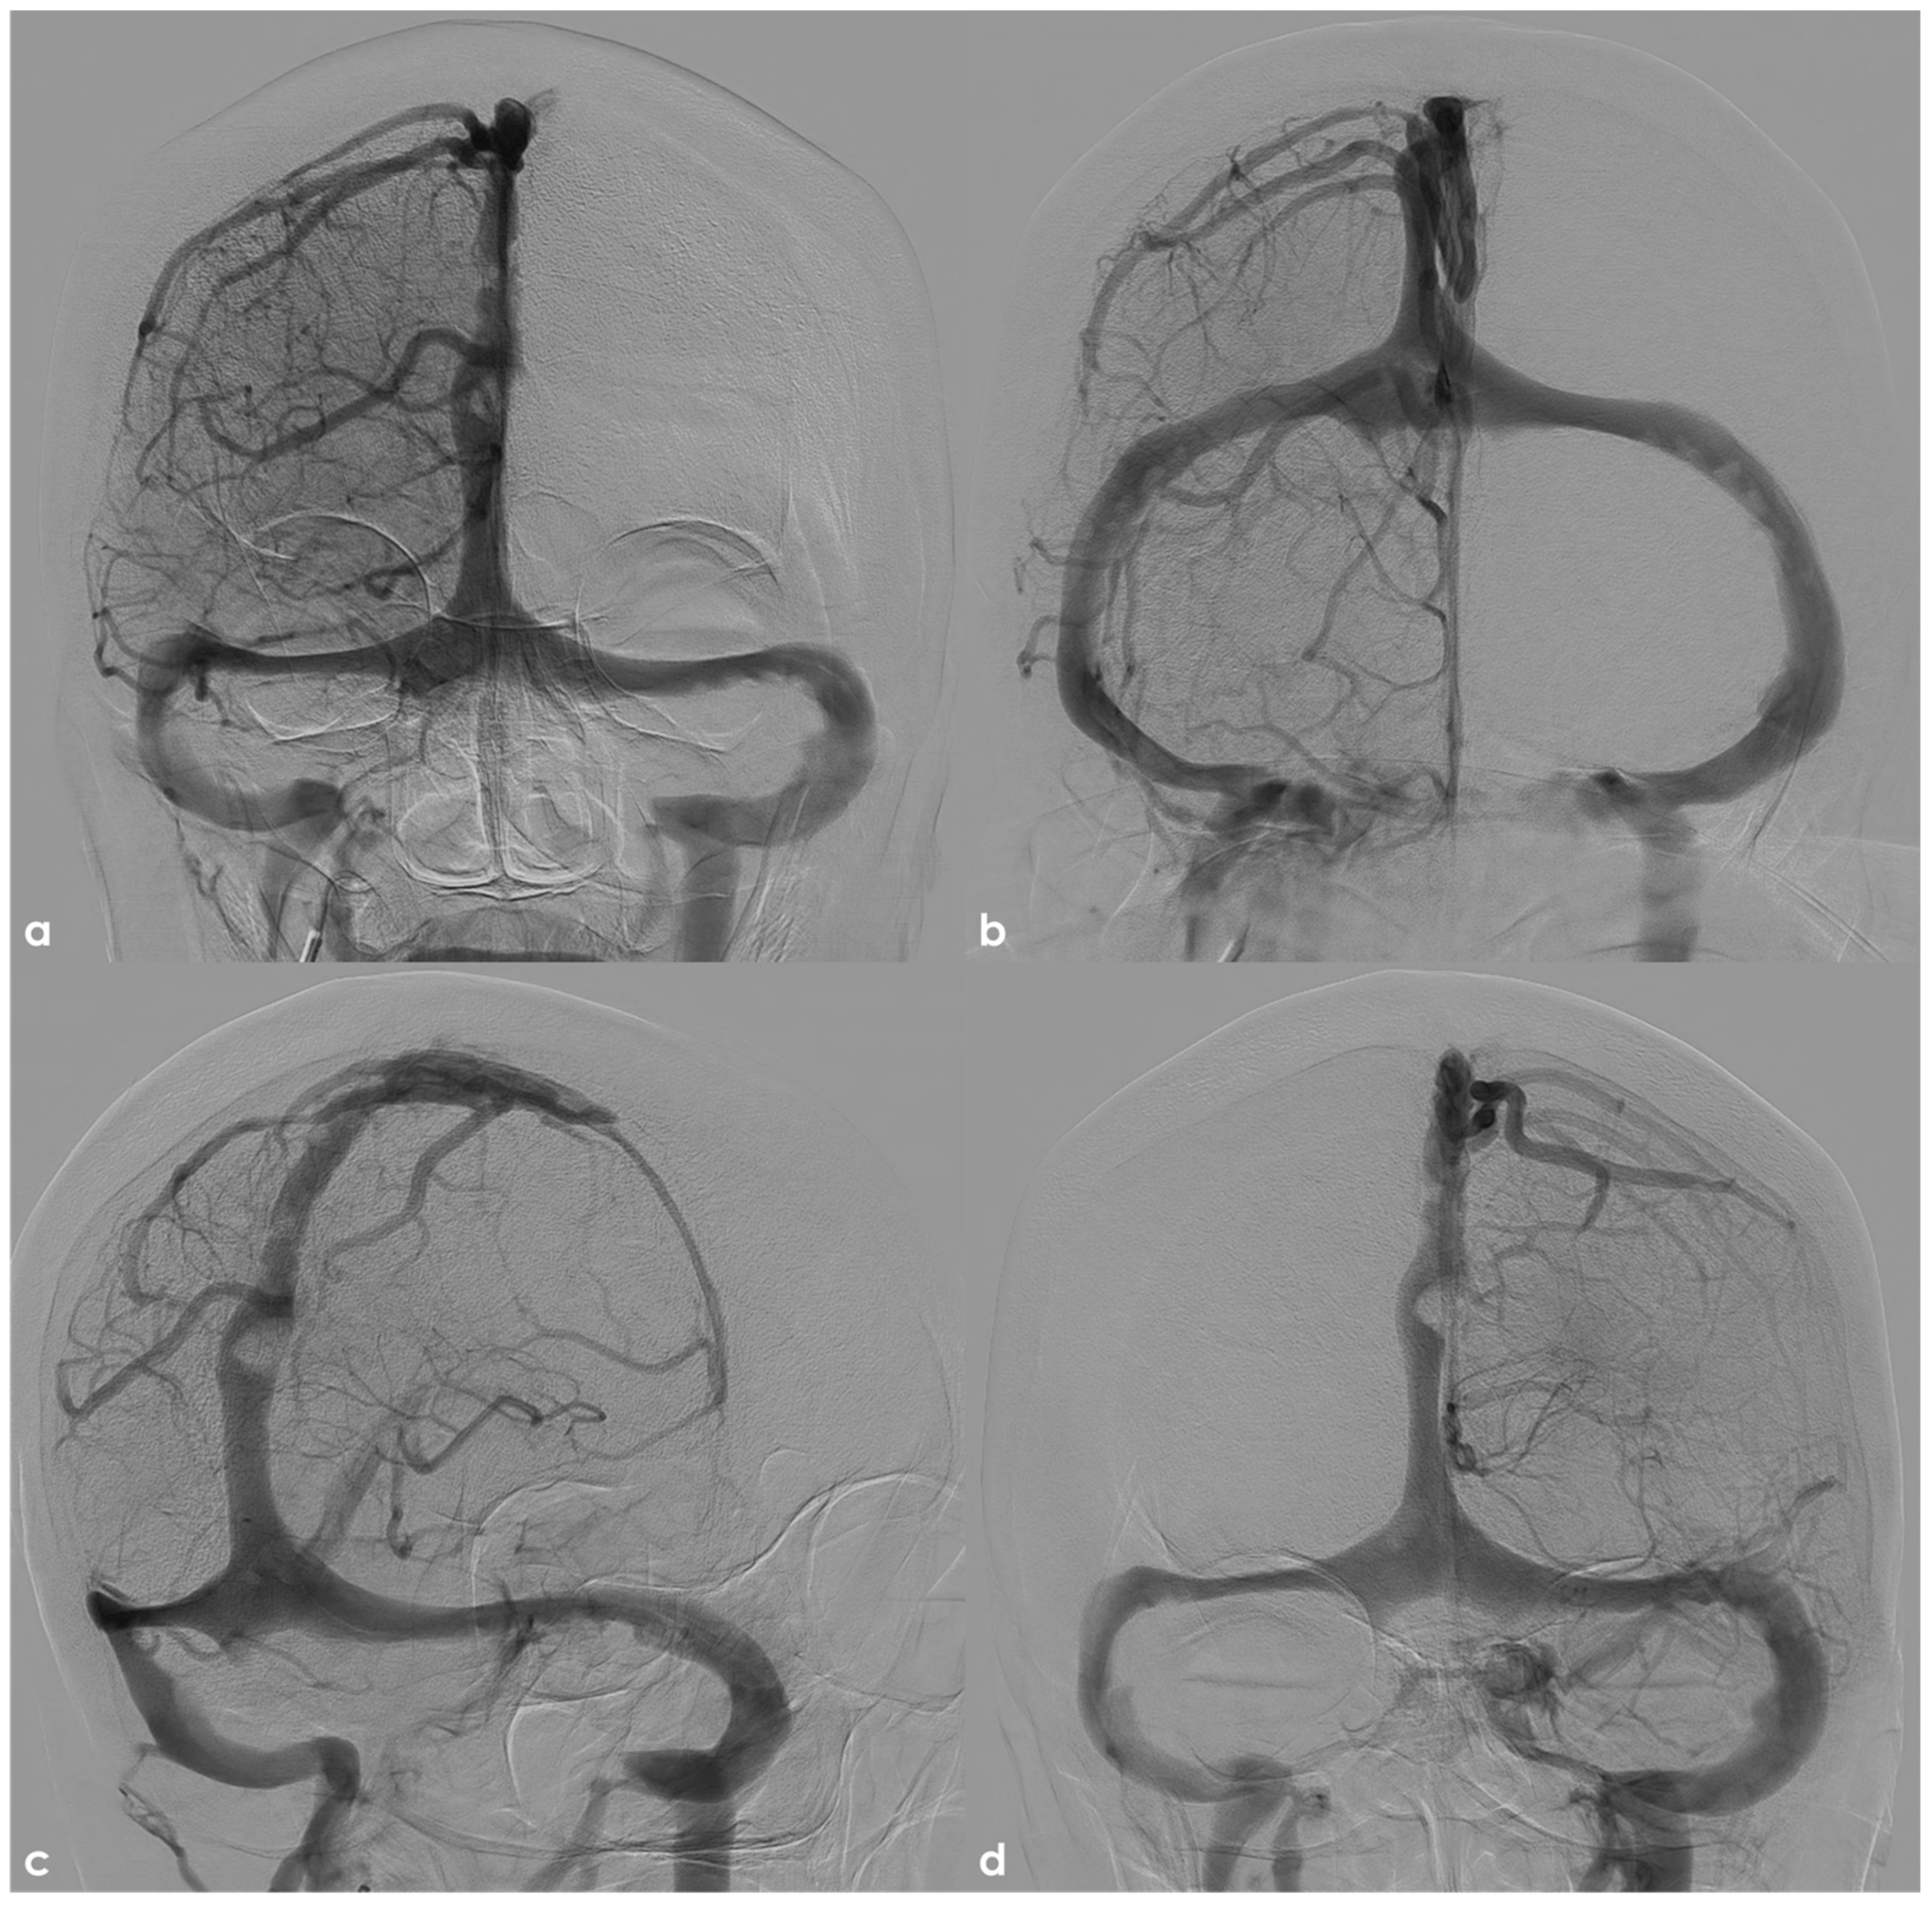

- Type I: this type has the highest incidence and often exhibit a strong double-lumen sign on DSA.

- -

- Type II: the second most common type: it is smaller in size and presents with a weaker imaging signal.

- Type III: the rarest type: it has less well-defined anatomical characteristics.